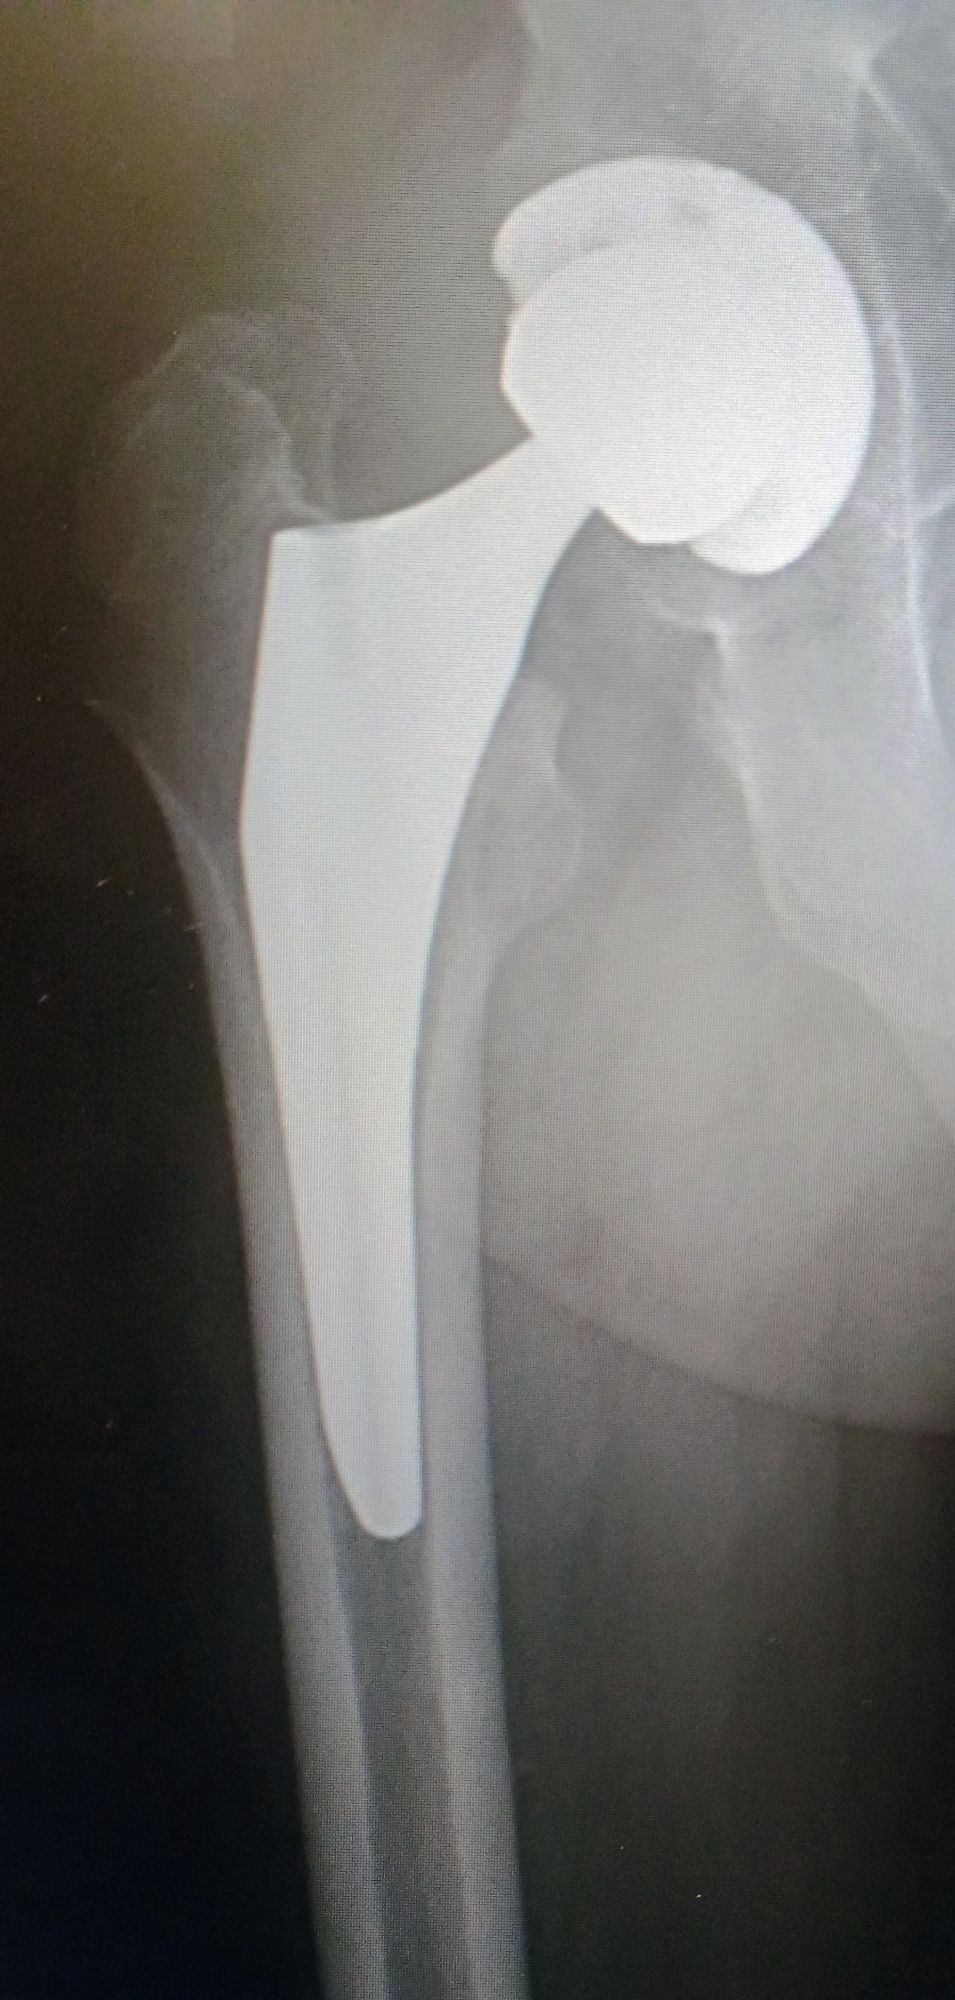

I chatted with them on and off trying not to disturb them. Answering questions as they asked. The sensations were very strange. I had seen this surgery many times before and knew what to expect. I could feel tugging and pushing and pulling on my body but there was no sensation of pain or otherwise. I could hear them drilling with a rasp the place for the cusp. I could feel them tugging on my leg as they inserted the titanium rod. I could feel them pounding the rod into place. All this again was without pain just a sensation of my body vibrating and movement.

There were a couple times at specifically 3 weeks and 5 weeks where I thought I might have done something damaging because the pain was extreme. The last time there was a lot of pain in the exterior of my thigh muscle and at the hip. They wanted to see me and do x-rays and said everything was perfect. Then they said they didn’t want to see me again for several months. I was free to do whatever I wanted. When we came to Florida, I was 7 weeks. I’ve been faithfully walking, riding a bicycle and going to the gym. I’ve been off pain medication for quite some time now. Only the occasional Advil or Tylenol.